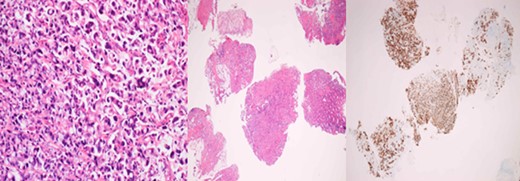

A 43-year-old female, 10 weeks postpartum, underwent colonoscopy for bleeding per rectum showing a bulky tumour (Fig. 1) in the rectum at 5 cm. Histologically poorly differentiated adenocarcinoma of the rectum (Fig. 2) T3N1Mo. Underwent laparoscopic loop ileostomy formation for impending bowel obstruction. Bloods showed Hemoglobin13.6 g/dL, Bilirubin 10umol/L, CEA 3.6 ng/mL. MRI pelvis (Fig. 3a and b) showed locally advanced annular neoplasm of mid and upper rectum. CT TAP (Fig. 4) reported no distant metastasis. She had neoadjuvant chemoradiothreapy with poor response. Post chemotherapy she noticed a lump in her right breast and axilla. Breast mammogram (Fig. 5a) showed 26 mm lesion in the right breast at 10 o'clock position and ultrasound showed 27 mm lesion in right axilla. Core biopsy (Fig. 6) reported signet ring morphology. The tumour stained positive with CK20, CDX-2 and CEA. There was no staining with CK7, ER, PR or Her-2. The rectal biopsy specimen, also analysed for KRAS status, was KRAS/NRAS/BRAF negative. She is being followed up by oncology with FOLFOX+Panitumumab.

Breast core biopsy showing features similar to the primary rectal cancer.

Histologically, the metastatic tumours show the morphological characteristics of the primary tumours. Excisional or incisional biopsy is the most commonly used procedure for the differential diagnosis [10]. There is increasing use of needle core biopsy rather than fine needle aspiration cytology. Silverman in his study reported 2529 FNA breast biopsies, 666 were malignant, only 18 of these were from extra-mammary malignancies. Alvardo et al. in his series of 10 650 breast biopsies in Mexican population, reported 24 extra-mammary cases.

In majority cases, immune-histochemistry can help to make an accurate diagnosis. Testing for expression of CK7 and CK20 is considered to be most beneficial. The great majority of primary breast cancers are CK7-positive and CK20-negative, while colorectal carcinomas are usually CK7-negative and CK20-positive. Mucinous differentiation of colorectal cancer is associated with poor outcome. In our patient, rectal tumour showed mucinous differentiation with features of signet ring cell subtype which explains the poor response to the neoadjuvant chemotherapy.